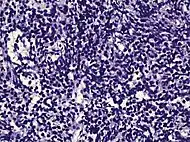

| Urothelial carcinoma | 0.7 to 2.8%[12] | ![]() |

Not recommended[1] | |||